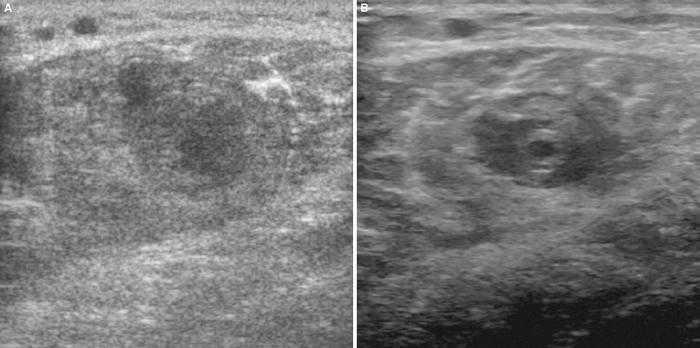

Utilizando el equipo E-A, mediante corte transverso sobre el músculo contusionado se observa (fig. 1A) la imagen de predominio hiperecoico y en su interior la zona oval hipoecoica con mala delimitación de los bordes y con mala definición del contenido, lo que la hace compatible con un lesión muscular por mecanismo extrínseco. La imagen del equipo E-B presenta también un aspecto hiperecoico, si bien la zona oval hipoecoica/anecoica presenta bordes muy bien marcados y se observa con detalle que en el interior existe un contenido heteroecoico que corresponde a las zonas de reabsorción del hematoma (fig. 1B). Todos estos signos permiten el diagnóstico preciso de la lesión muscular extrínseca.

Figura 1 A) En el corte transverso con E-A se observan imágenes hipoecoicas en el vientre del músculo gastronemio interno. B) En el mismo corte, con el equipo E-B se delimita exactamente la zona lesionada del área muscular indemne que lo rodea.